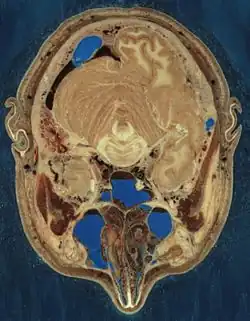

Der männliche Körper wurde gefroren und anhand eines Intervalls von einem Millimeter in 1871 axiale Schnitte zerlegt. Diese wurden fotografiert, die Bilder wurden anschließend digitalisiert. Das gesamte Datenvolumen aller Bilder, die jeweils eine Auflösung von 2048 × 1216 Pixeln in 24 Bit Farbtiefe haben, beträgt 15 Gigabyte. Im August 2000 wurden Daten mit einer höheren Auflösung zur Verfügung gestellt. Dazu wurden Fotos von Teilausschnitten der Körperschnitte mit einer Auflösung von 4096 × 2700 Pixeln digitalisiert und entsprechend zusammengesetzt. Daraus ergibt sich ein Datenvolumen von 65 Gigabyte. Der weibliche Körper wurde in einem Intervall von 0,33 Millimetern geschnitten, woraus sich 5189 Schnitte und 40 Gigabyte Daten ergaben.

Zusätzlich wurden mittels Computertomographie in einem Intervall von einem Millimeter und Magnetresonanztomographie in einem Intervall von vier Millimetern weitere Abbildungen der Körper in verschiedenen Ebenen gewonnen. Alle Arbeiten fanden am Zentrum für Gesundheitswissenschaften der Universität von Colorado statt.

Das Gehirn des männlichen Körpers schwoll durch den Gefrierprozess leicht an. Teile seiner Innenohren sind während des Schneideprozesses verloren gegangen. Nerven sind in den Schnitten kaum von Fettgewebe zu unterscheiden. Kleine Blutgefäße sind durch den Gefrierprozess kollabiert und zeigen somit nicht die natürliche Struktur. Der Spender besaß darüber hinaus nur einen Hoden. Die Geschlechtsorgane der Frau sind aufgrund ihres Alters nicht repräsentativ für die einer jungen Frau.